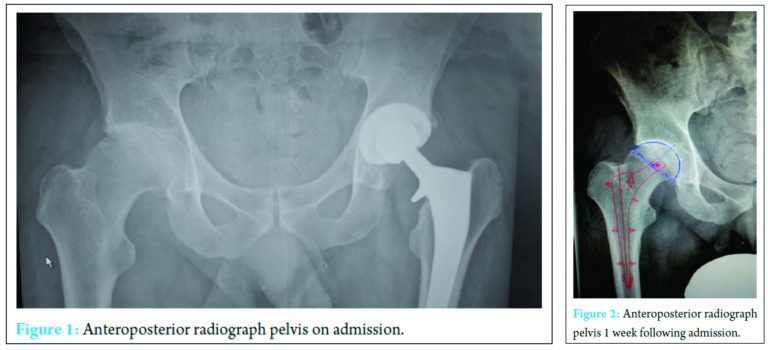

A 59-year-old physical education teacher with known right hip osteoarthritis was admitted with rapid onset of increasing right hip pain, inability to weight bear, pyrexia, and rigors. Relevant medical history included a successful left total hip arthroplasty, hemochromatosis, and hypercholesterolemia. There was no evidence of liver cirrhosis. Blood markers were elevated with a neutrophil leukocytosis of 24 × 103 cells/mm3 and C-reactive protein (CRP) of 514 mg/ml. Normal range 0-5 mg/ml (Fig. 1). Radiographs demonstrated right hip osteoarthritis while an ultrasound scan demonstrated a large echogenic right hip effusion with associated synovial thickening. The patient was managed with an urgent washout and debridement of his right hip joint through an anterior approach. Intraoperatively, intravenous teicoplanin 400 mg was commenced following collection of multiple fluid and tissue samples. A closed suction drain was left in situ that collected 200 ml of serosanguinous fluid in the first 24 h after which the drain was removed. Two pre-operative peripheral blood cultures and four separate fluid and tissue theater samples grew S. aureus, sensitive to flucloxacillin and sodium fusidate. Microbiology advised switching from intravenous teicoplanin 400 mg TID to intravenous flucloxacillin 2 g QDS and oral sodium fusidate 500 mg TID. He initially responded well with falling inflammatory markers, apyrexia, pain reduction, and a dry healing wound (Fig. 2).